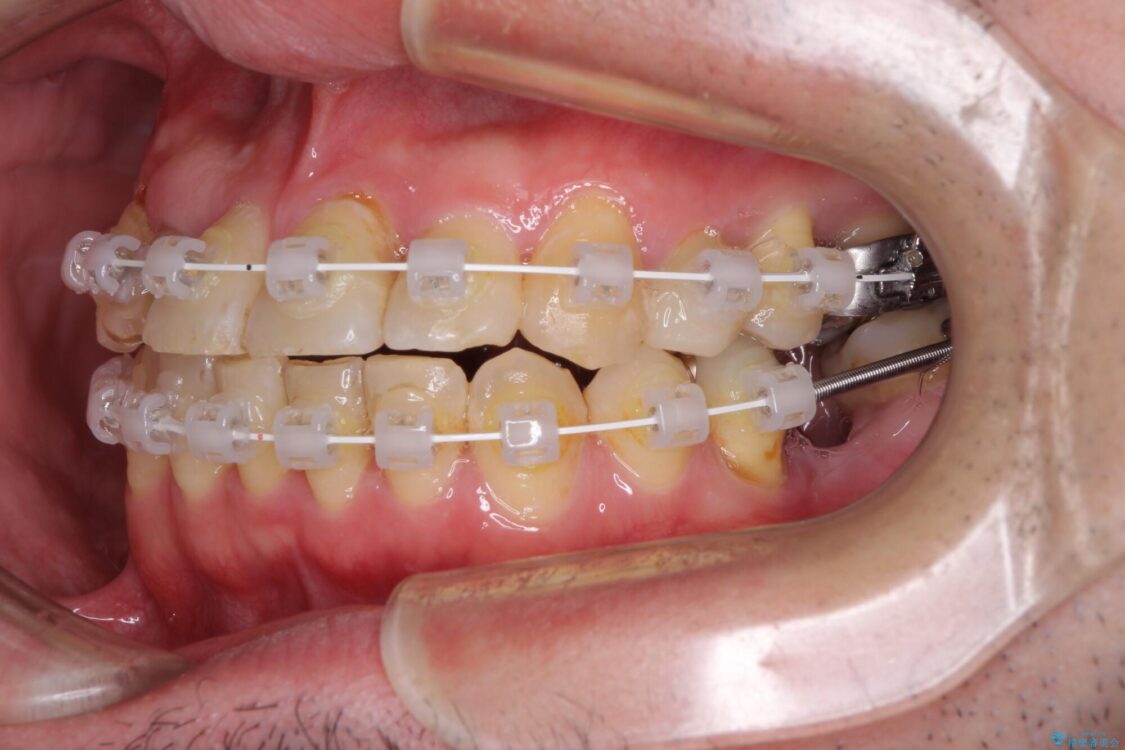

治療途中

• 割れてしまった奥歯とデコボコの前歯 矯正治療とインプラント治療 治療途中画像